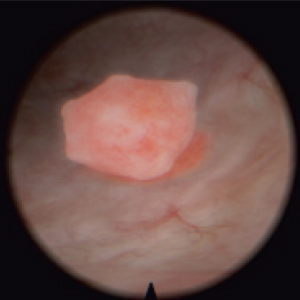

Diagnostic and surgical skills in Hysteroscopy & TUR

Resectoscope for hysteroscopy

Real resectoscope handle. Pedals for coagulation and electric dissection.